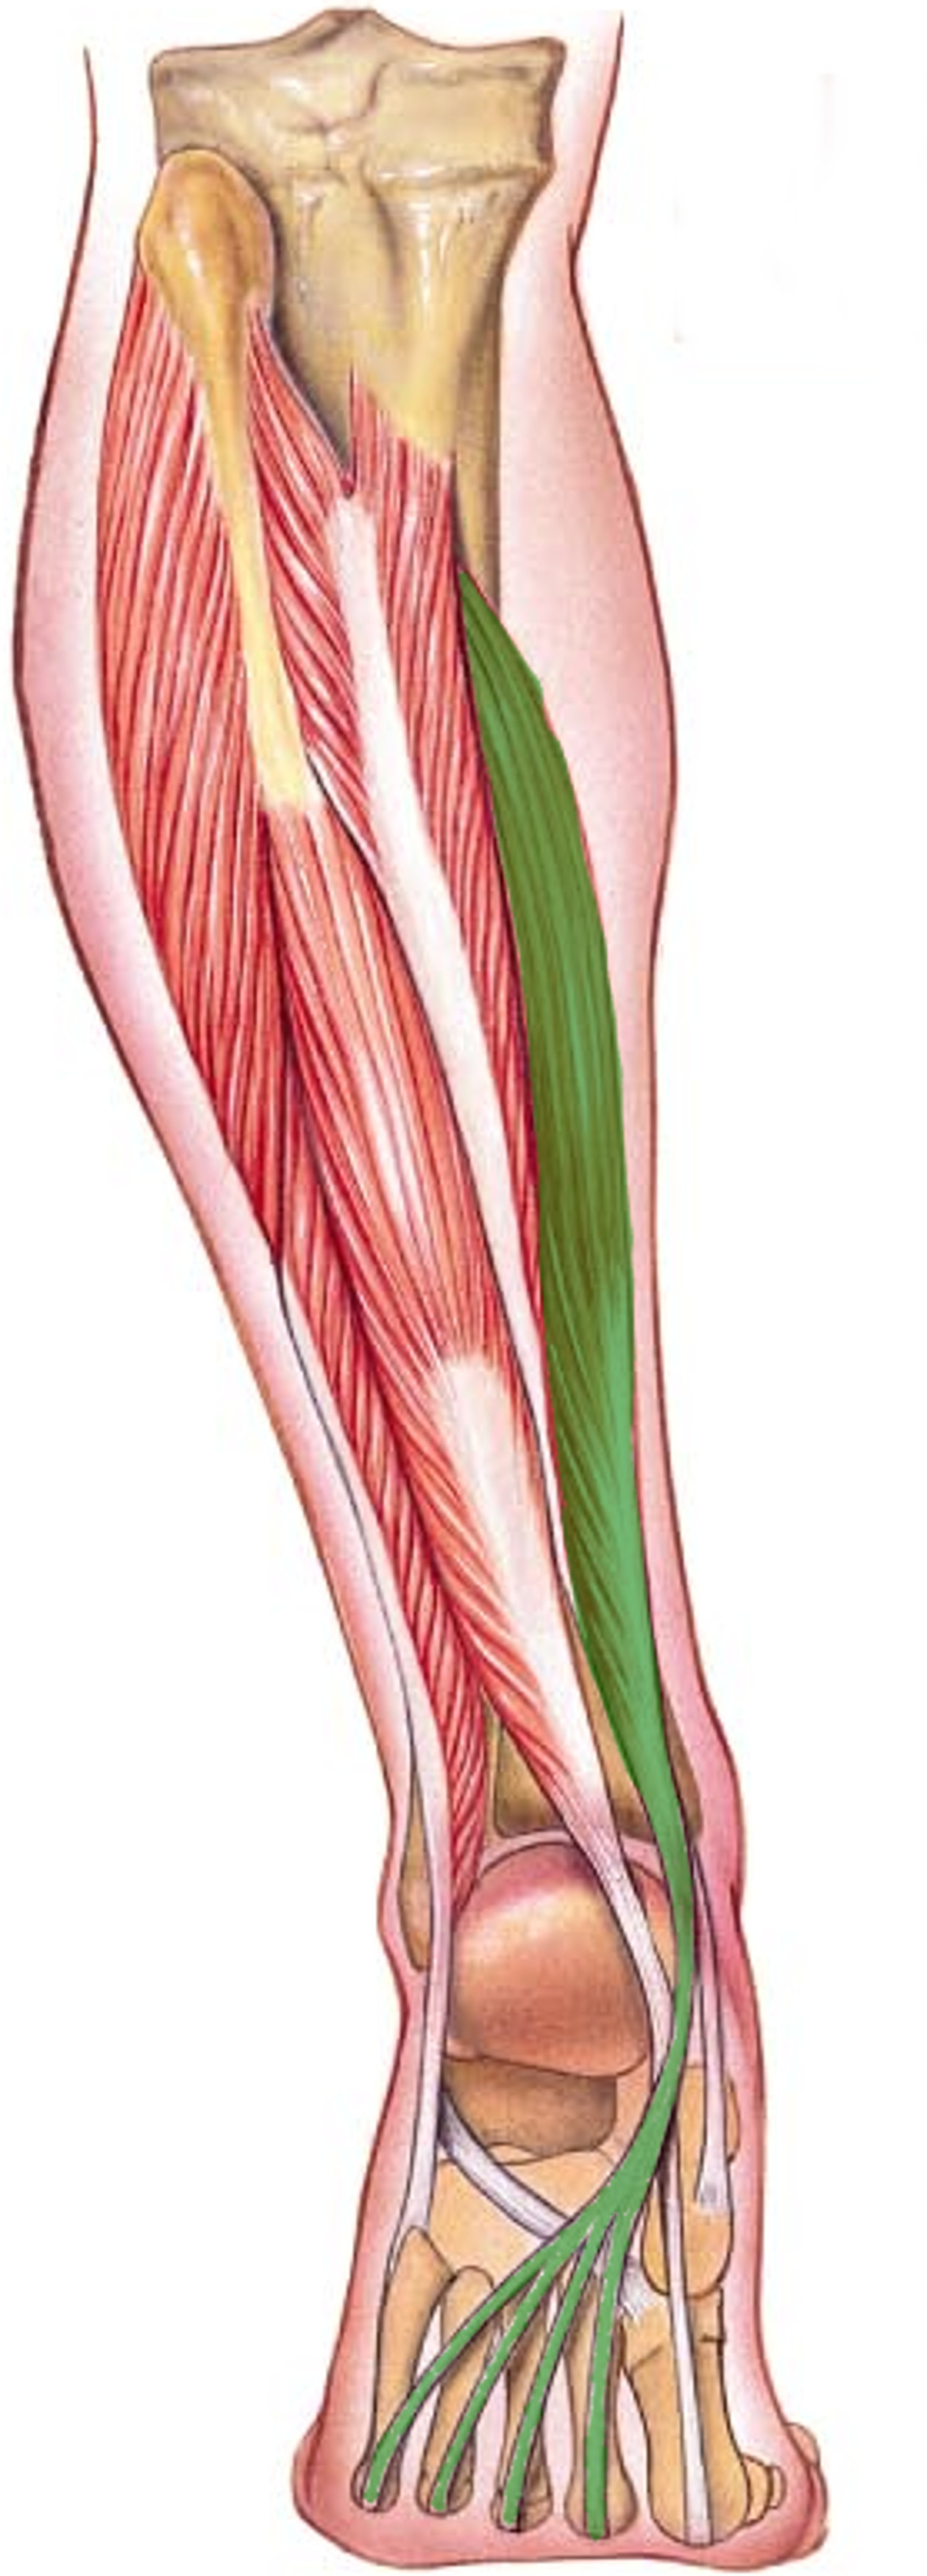

What is the innervation of this muscle?

Muscle - Flexor digitorum longus

Tibial nerve

L5 - S2